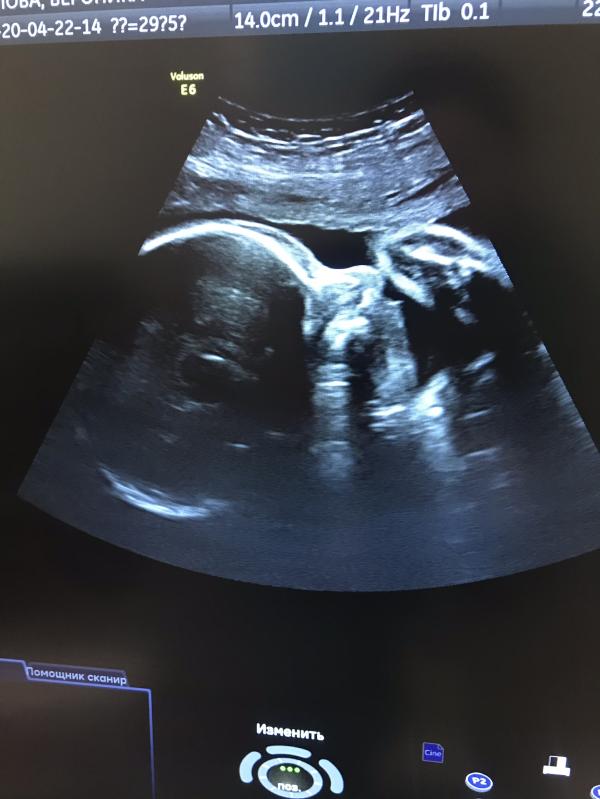

Вчера ездила в 25 роддом на скрининг😊

Посмотрели нашего мальчика, Слава Богу все хорошо. Такой он сладкий, хочется уже скорее встретиться с ним🤪

По узи сказали, что рожать примерно 7 июля, значит числа 15 рожу, я как слониха, ношу до последнего(